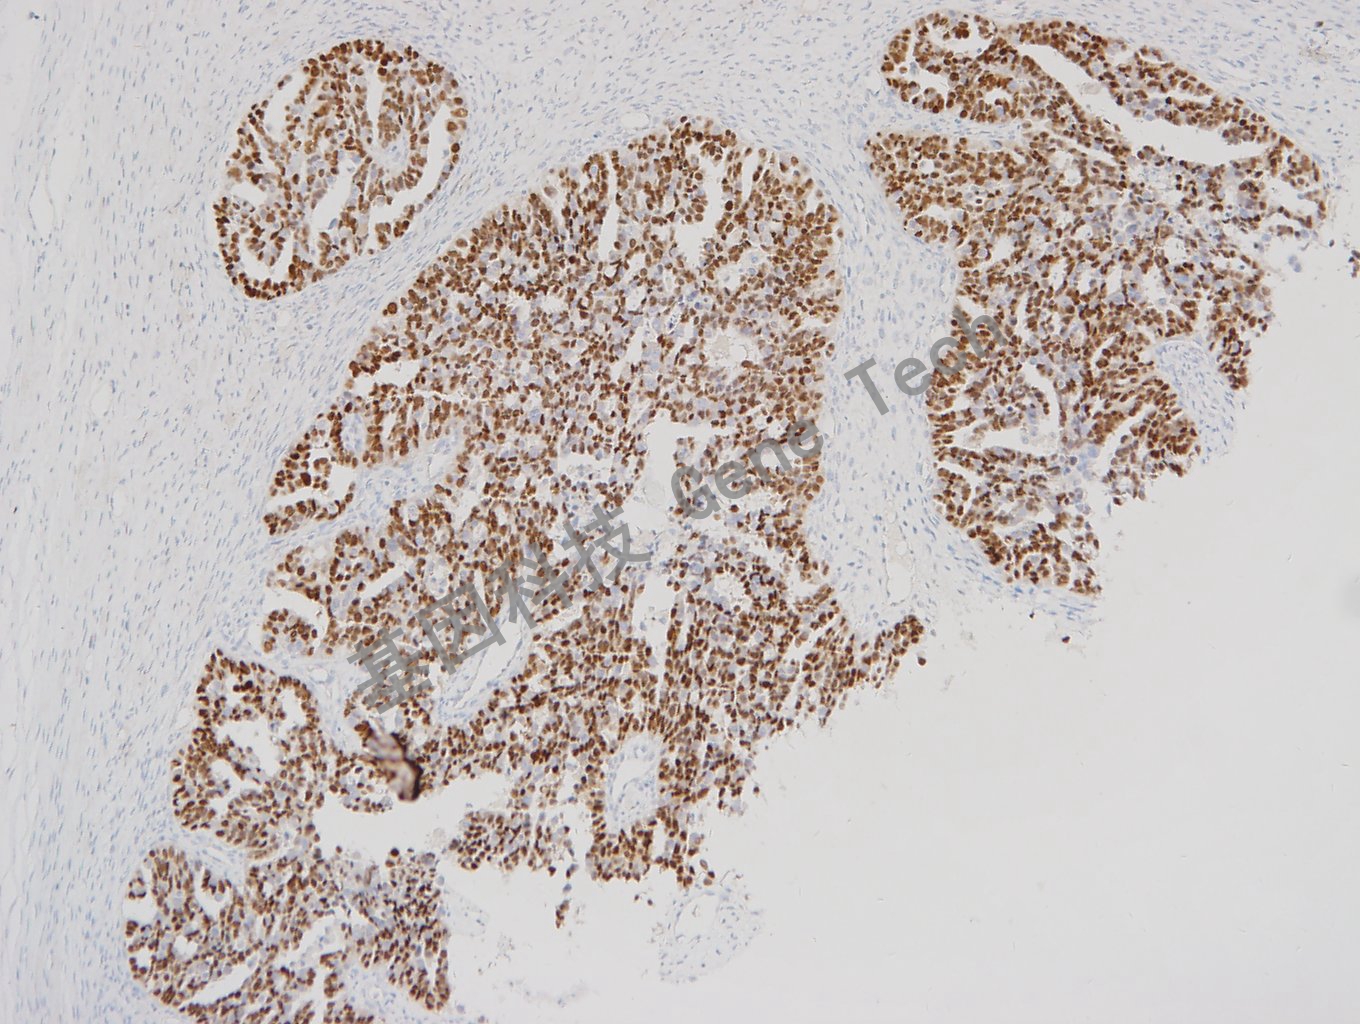

卵巢癌石蜡切片,用 Pax-8(GT2102)染色,细胞核阳性,DAB 显色。